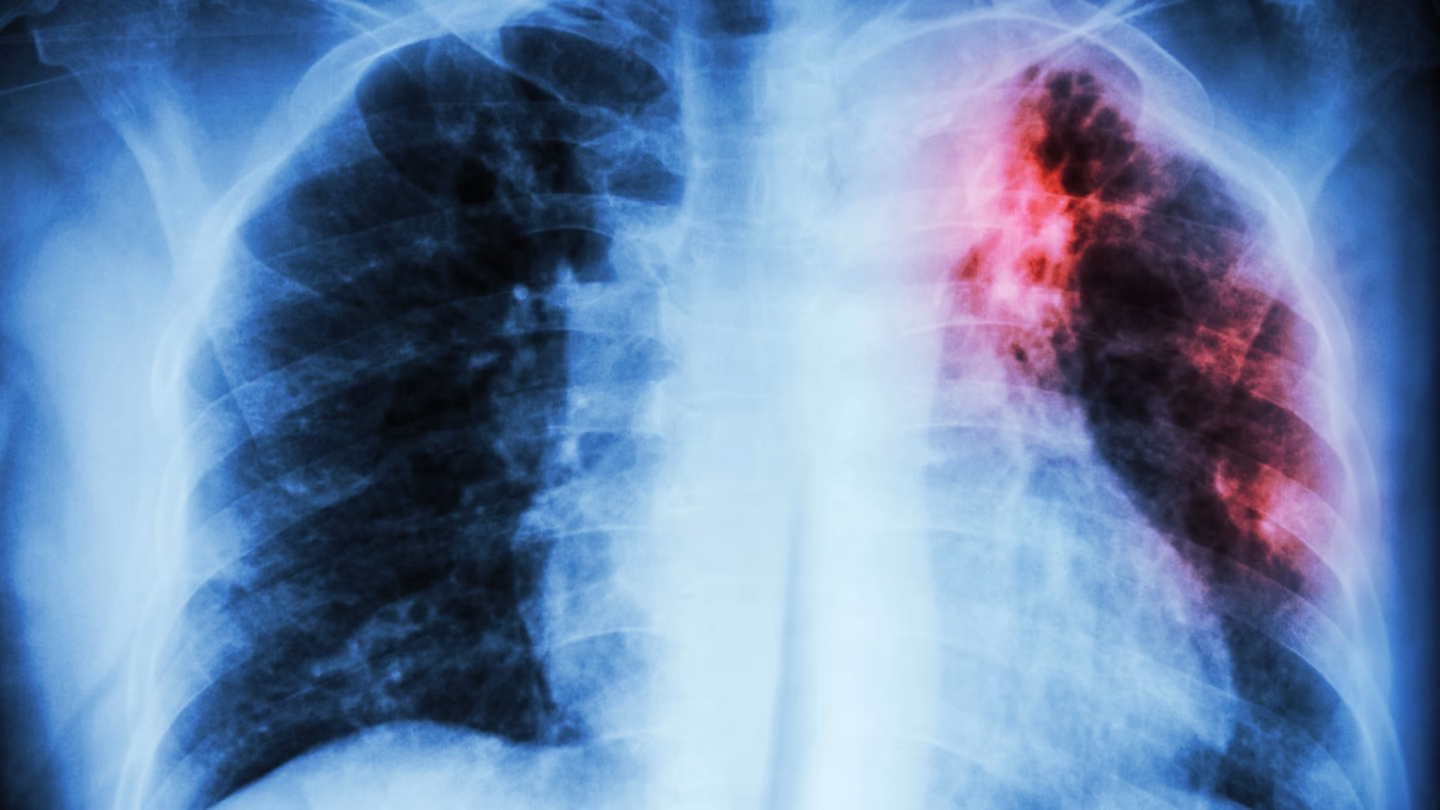

| Diagnostisk Test | Positiv hud-/blodprøve, positiv spytprøve, unormalt røntgenbillede af brystet | Positiv hud-/blodprøve, normal spytprøve og røntgenbillede af brystet | Dokumentation fra tidligere positive tests og/eller behandling. |